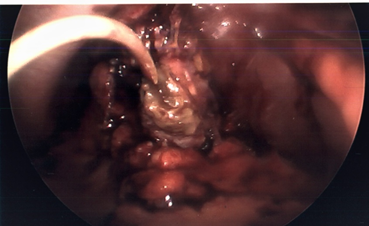

Patient was readmitted about 6 weeks later with acute changes in mental status, secondary to acute aspiration pneumonia. He developed bilateral pleural effusions and had a right-sided thoracocentesis performed. Around this time, his IR cholecystostomy drain fell out, and his liver function tests started to trend up - suggestive of ongoing acute on chronic cholecystitis. He underwent an ultrasound scan at this time which failed to visualize the gallbladder due to extensive distention of bowel gas shadows. Hence IR could not reposition the percutaneous drain. He was therefore taken to the operating room for planned laparoscopic cholecystectomy, after his acute medical condition was stabilized. Intraoperatively, there were extensive dense adhesions around the gallbladder. The gallbladder itself appeared thickened, contracted and was very friable (Figure 1). Attempt to dissect the cystic duct and cystic artery was deemed unsafe due to the significant adhesions and poor tissue friability. Hence decided to perform LCtube placement. A 12 French Foley catheter was inserted through one of the 5 mm port sites and placed into the fundus of the gallbladder. The balloon was then inflated within the gallbladder to secure it in place (Figure 2). A Jackson Pratt (JP) drain was inserted adjacent to it in the gallbladder fossa.

Figure 1 Severe acute cholecystitis.